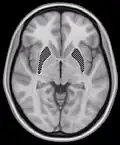

Horizontal slice of MRI-image showing the putamen. The other nuclei of the basal ganglia (caudate nucleus and globus pallidus) can be seen as well.- Putamen